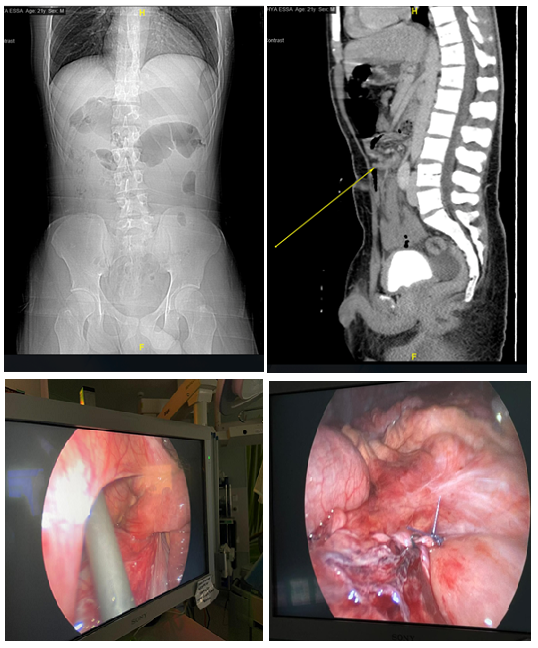

Open AccessCase Report

Right Paraduodenal Hernia: A Case Report and Literature Review

Dr. Norah Alabdulaaly, Dr. Mohammed Ali Alshehri, Dr. Feras Alsannaa

International Journal of Innovative Research in Medical Science·March 21, 2022